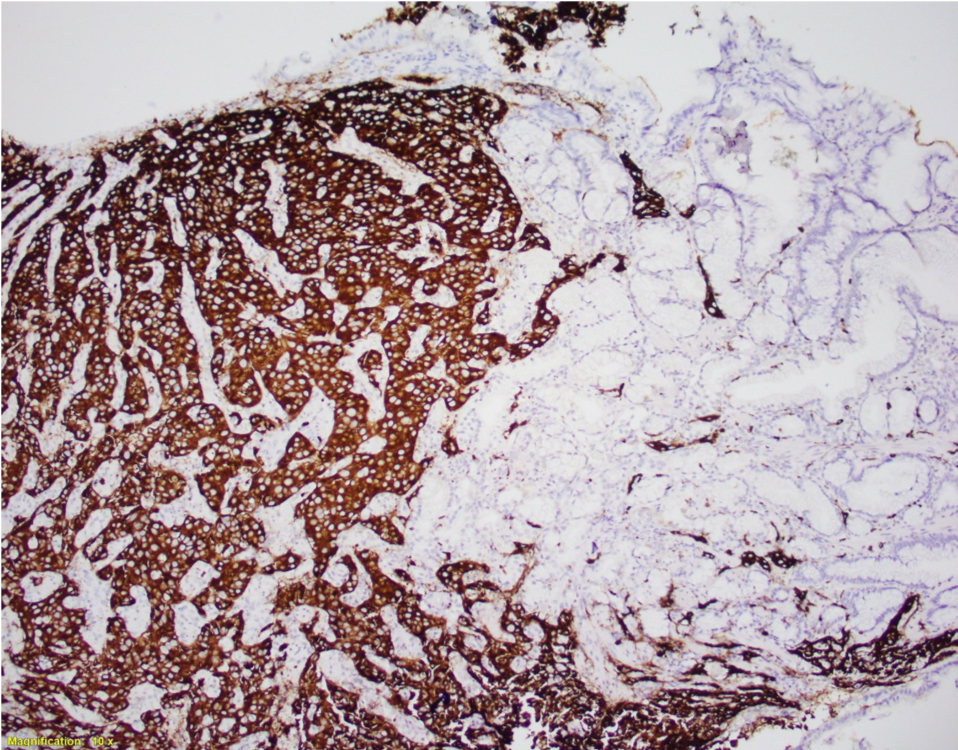

A 56-year-old female underwent upper endoscopy for dyspepsia. A 1 cm gastric nodule was found and biopsied. The histological findings are shown in Figure1 (low power) and Figure 2 (high power). Synaptophysin immunostaining of the tumor (Figure 3) and the background mucosa (Figure 4) are included.

This NET is occurring in a background of atrophic oxyntic mucosa, also known as autoimmune metaplastic atrophic gastritis ( AMAG), which typically shows nodular neuroendocrine cell hyperplasia (ECL) highlighted by synaptophysin stain ( Figure 4}. Intestinal metaplasia is also seen in Figure 1. Psedopyloric metaplasia (another characteristic) feature cannot be appreciated in the provided photographs. Even though Gastrin stain is not provided, the staining pattern of neuroendocrine cells is not that of G cells. Type 1 gastric NETs are typically small, multiple, low grade, associated with antibodies for intrinsic factor/ parietal cell, often have iron deficiency or B12 deficiency, and are managed by endoscopic surveillance. Type 3 NETs are sporadic, not associated with atrophic corpus gastritis. Type 2 are rare, can show ECL hyperplasia, but are associated with MEN1/gastrinoma and parietal cell hyperplasia.